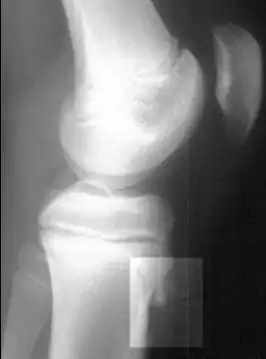

![]() Рентгенограмма коленного сустава в боковой проекции, демонстрирующая фрагментацию большеберцовой бугристости с отёком окружающих мягких тканей.Разрушение костной ткани . | |

- Рентгенографическое исследование коленных суставов в боковых проекциях; часто наблюдаются характерные «хоботки» в области бугристости большеберцовых костей, нередко вводящие врачей в заблуждение; изолированные костные фрагменты небольших размеров, иногда в количестве 1-2-3. Картина представляется очень разнообразной, напоминающей дробления, искривления и надломы эпифизарного отростка.